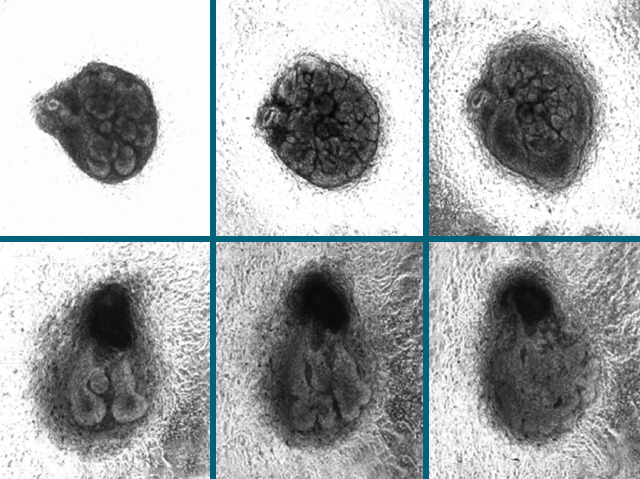

Our eyes are protected by a tear film produced by a lacrimal gland and leaked into our eyes via tear ducts. This gland secretes water, for eyelid lubrication, and various proteins, which both moisturise the eyes and kill off any harmful microorganisms. A malfunction of the lacrimal gland will lead to dry eye disease and consequential damage to the protective tissue lining the front of the cornea. This is extremely uncomfortable for the sufferer and will result in substantial vision loss. Current treatments, including eye drops of artificial tears, are not ideal. However, recent research efforts have led to the development of a fully functioning bioengineered lacrimal gland. When engrafted into the natural lacrimal gland of mice it successfully replaces its function. Here we see time-lapsed development (left to right) of the natural lacrimal gland (top row) and the bioengineered version (bottom row).